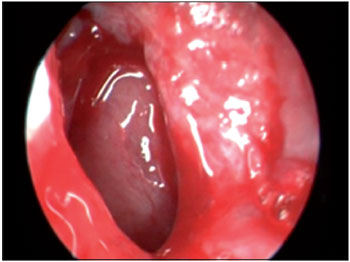

Figure 5. Intraoperative endoscopic visualization of the right nasal cavity demonstrating septal resection to allow approach to the bone wall of the pneumatized crista galli.

SEPTO = nasal septum; CM = middle turbinate.

FFigure 6. Intraoperative endoscopic visualization of the right nasal cavity showing transseptal opening of the bone wall of the pneumatized crista galli.

SEPTO = nasal septum; CM = middle turbinate.

Figure 7. Intraoperative endoscopic visualization of the right nasal cavity demonstrating the detail of opening of the pneumatized crista galli, the lining of which shows mucosal thickening and edema.